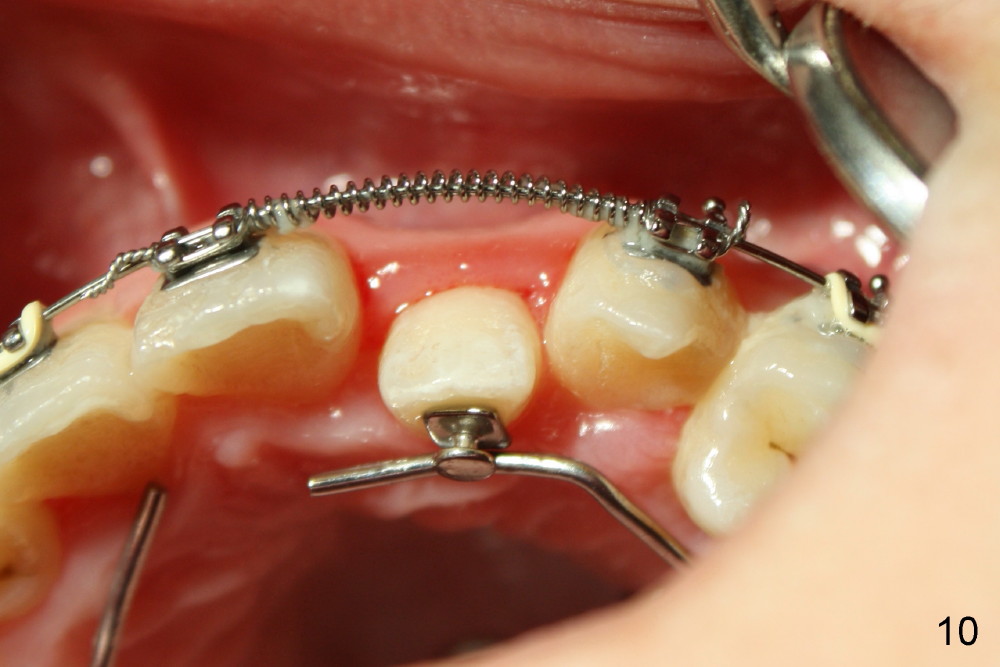

Two months installing open coil between UL 1 and 3, the space for UL2 is not increased enough. In addition, posterior cross bite is not corrected by arch expansion. Nitanium palatal expander is placed. One month later, the posterior cross bite appears to have been improved. The space for UL2 increases significantly (Fig.10); a sling shot is installed (Fig.11).